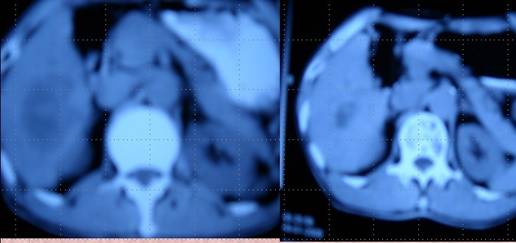

XX,男,67歲,退休工人,家住黑龍江雞西市。該患于20083月因肝左葉癌在哈爾濱醫科大學二院行肝左葉切除術,術后三個月復查肝CTMRI示肝右葉轉移,遂于當地礦務局總醫院做了一次血管介入化療栓塞治療。三個月后復查再次出現肝右葉3個轉移灶,其中最大的直徑達5.5cm,又在雞西市中醫院腫瘤科做了一次射頻消融治療。當時只對最大的轉移灶進行了處理,小的沒做處理,患者從確診以來一直在積極求治,結果是一邊治療一邊轉移,最后一次治療結束后,家屬決定讓病人試一試中醫。于是該患者于200811月末開始到市中醫院腫瘤科求治與本人,經采用“董氏調胃、強腎、止血、化巖治癌法”治療,患者服藥2個月后復查肝CT及彩超均未提示肝臟有另外兩個小轉移灶,而最大的轉移灶也明顯變小為2.5x3cm,繼續治療三個月復查肝CTMRI均提示射頻消融術后改變。之后多次復查均為肝左葉切除術后改變,肝右葉射頻消融術后改變。回訪至今患者一切如常,患者已無病生存3年。

肝癌病人楊XX采用“董氏治癌法”治療前后 CT對照變化